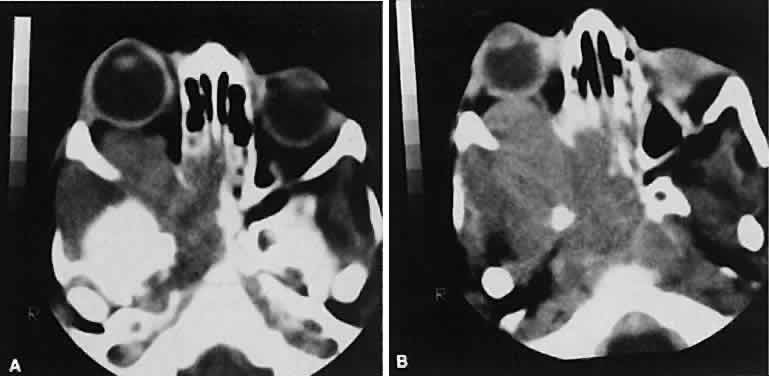

Dermoid cysts are located most frequently in the superior temporal quadrant of the orbit. They may be located anywhere within the orbital confines. Lesions in the lacrimal fossa or along the posterior lateral wall may communicate intracranially or into the temporalis fossa. Radiographically, the cysts are well-delineated and have lucent interiors with CT attenuation densities in the fat range (Fig. 19). Calcification along the rim of the cyst may be present. The bony changes have irregular, notched borders rather than the moth-eaten appearance associated with malignancy. The range of CT appearances can be quite wide.67

Fig. 19. Axial (A) and coronal (B) scans of a dermoid cyst. Note the low attenuation (lower than retrobulbar fat) within the well-demarcated cyst located in the right lacrimal gland fossa.